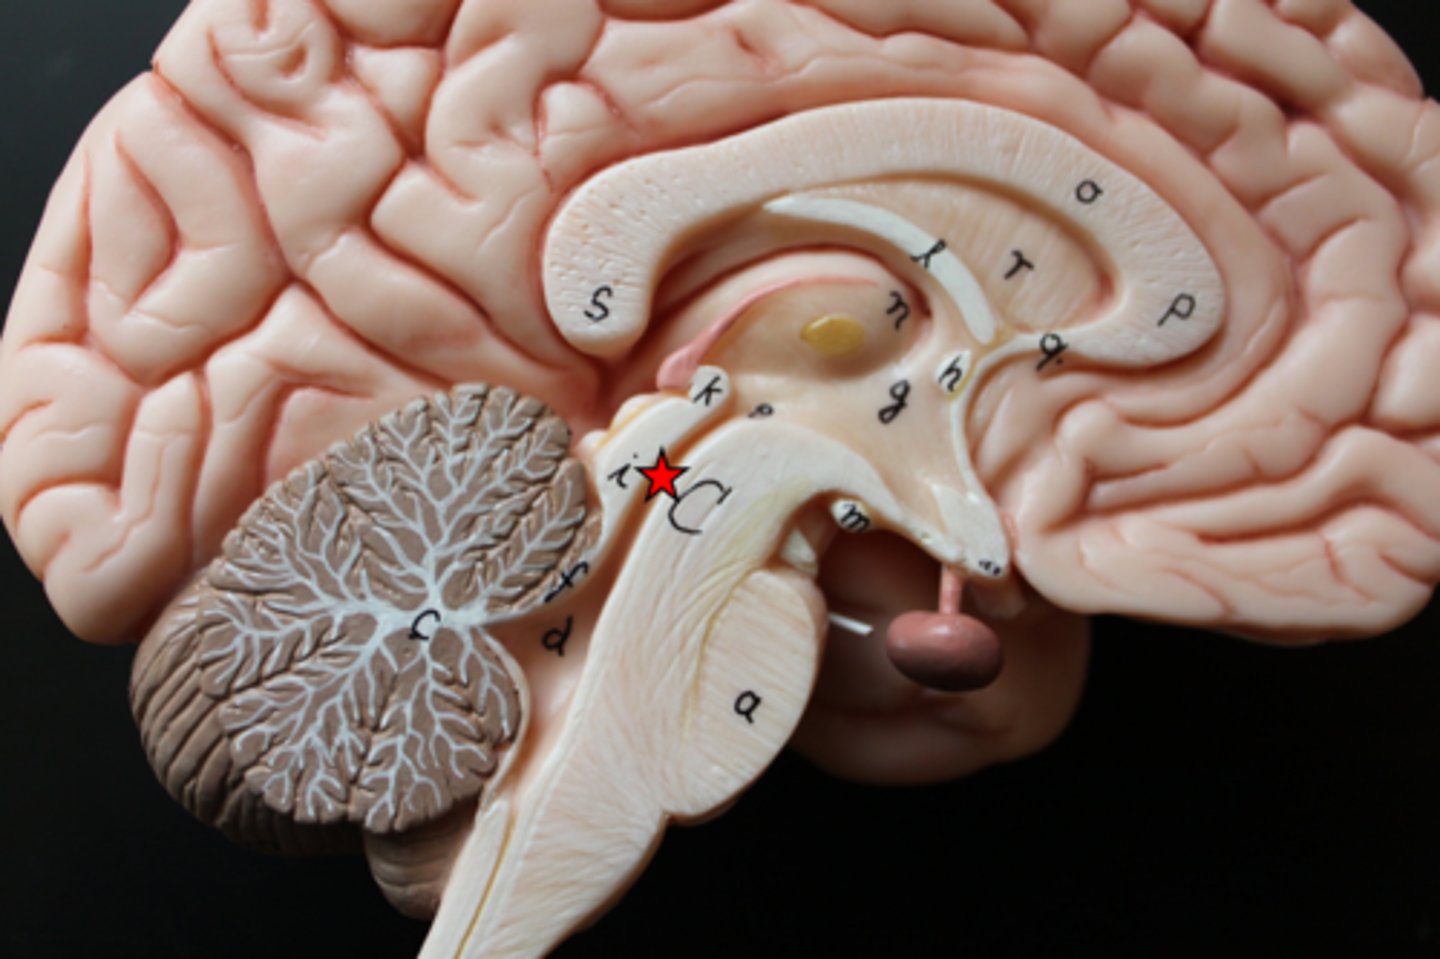

34 Terms

1

New cards

longitudinal fissure

2

New cards

frontal lobe

3

New cards

temporal lobe

4

New cards

parietal lobe

5

New cards

occipital lobe

6

New cards

central sulci

7

New cards

lateral sulci

8

New cards

gyri

9

New cards

cerebrum

10

New cards

corpus callosum

11

New cards

lateral ventricles

12

New cards

3rd ventricle

13

New cards

4th ventricle

14

New cards

cerebellum

15

New cards

thalamus

16

New cards

hypothalamus

17

New cards

midbrain

18

New cards

pons

19

New cards

medulla oblongata

20

New cards

cerebral aqueduct

21

New cards

I.

Olfactory

22

New cards

II.

Optic

23

New cards

III

Oculomotor

24

New cards

IV.

Trochlear

25

New cards

V.

Trigeminal

26

New cards

VI.

Abducens

27

New cards

VII.

Facial

28

New cards

VIII.

Vestibulocochlear

29

New cards

IX

Glossopharngeal

30

New cards

X.

Vagus

31

New cards

XI

Accessory

32

New cards

XII

Hypoglossal